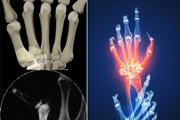

ارتز کشش دینامیک (ارتز آرتریت روماتوئید)شایع ترین دفورمیتی در بیماری آرتریت روماتوئید انحراف به سمت اولنار در دست و نیمه دررفتگی به طرف کف دست…

تغییر شکل سوان نک (گردن قوئی) در دست ناشی از آرتریت روماتوئید اعتقاد بر این است که این دفورمیتی بر اثر کانتر کچر عضلات عمقی دست ایجاد می شود. مفصل بین…

تغییر شکل بوتونیر در آرتریت روماتوئیددفورمیتی های بوتونیر و سوان نک از تغییر شکل های خاص بیماری آرتریت روماتوئید در دست می باشند. ممکن است…